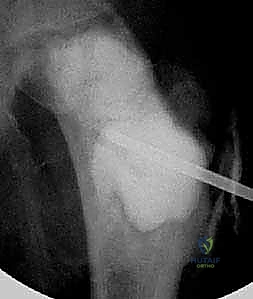

* حقن الكورتيكوستيرويد (Steroid Injections): يتم إدخال إبرتين تحت توجيه الأشعة السينية (Fluoroscopy). تُستخدم الإبرة الأولى لشفط السائل الكيسي، والإبرة الثانية لحقن مادة الكورتيزون (Methylprednisolone). يعمل الكورتيزون على تثبيط الخلايا المسببة لتآكل العظم، مما يسمح للعظم بالشفاء. قد يتطلب الأمر تكرار الحقن 2-3 مرات بفاصل بضعة أشهر.

استخدام تقنيات الحقن طفيفة التوغل تحت توجيه الأشعة السينية المباشرة، وهي خطوة أولى فعالة في علاج أكياس العظام أحادية الغرفة (UBC) لتجنب الجراحة المفتوحة متى ما أمكن ذلك.